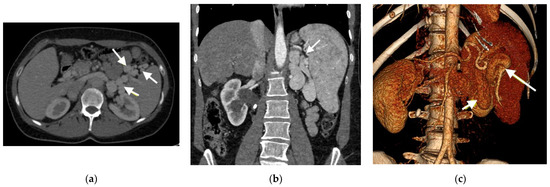

- Type I—end-to -side anastomosis with a complete portosystemic shunt exhibiting no visible portal flow in the liver due to the absence of intrahepatic portal veins. The malformation is female-predominant and associated with other congenital abnormalities, such as cardiac defects.

- Type II—side-to side-anastomosis with hypoplastic intrahepatic portal veins, and the liver is perfused with portal blood in the presence of a partial shunt (e.g., porto-hepatic venous anastomoses) [4].

- Laverdure, N.; Lallier, M.; Dubois, J.; Paganelli, M. Congenital Absence of the Portal Vein: Define the Portosystemic Shunt, Avoid Liver Transplantation. CanLivJ 2021, 4, 322–327. [Google Scholar] [CrossRef] [PubMed]